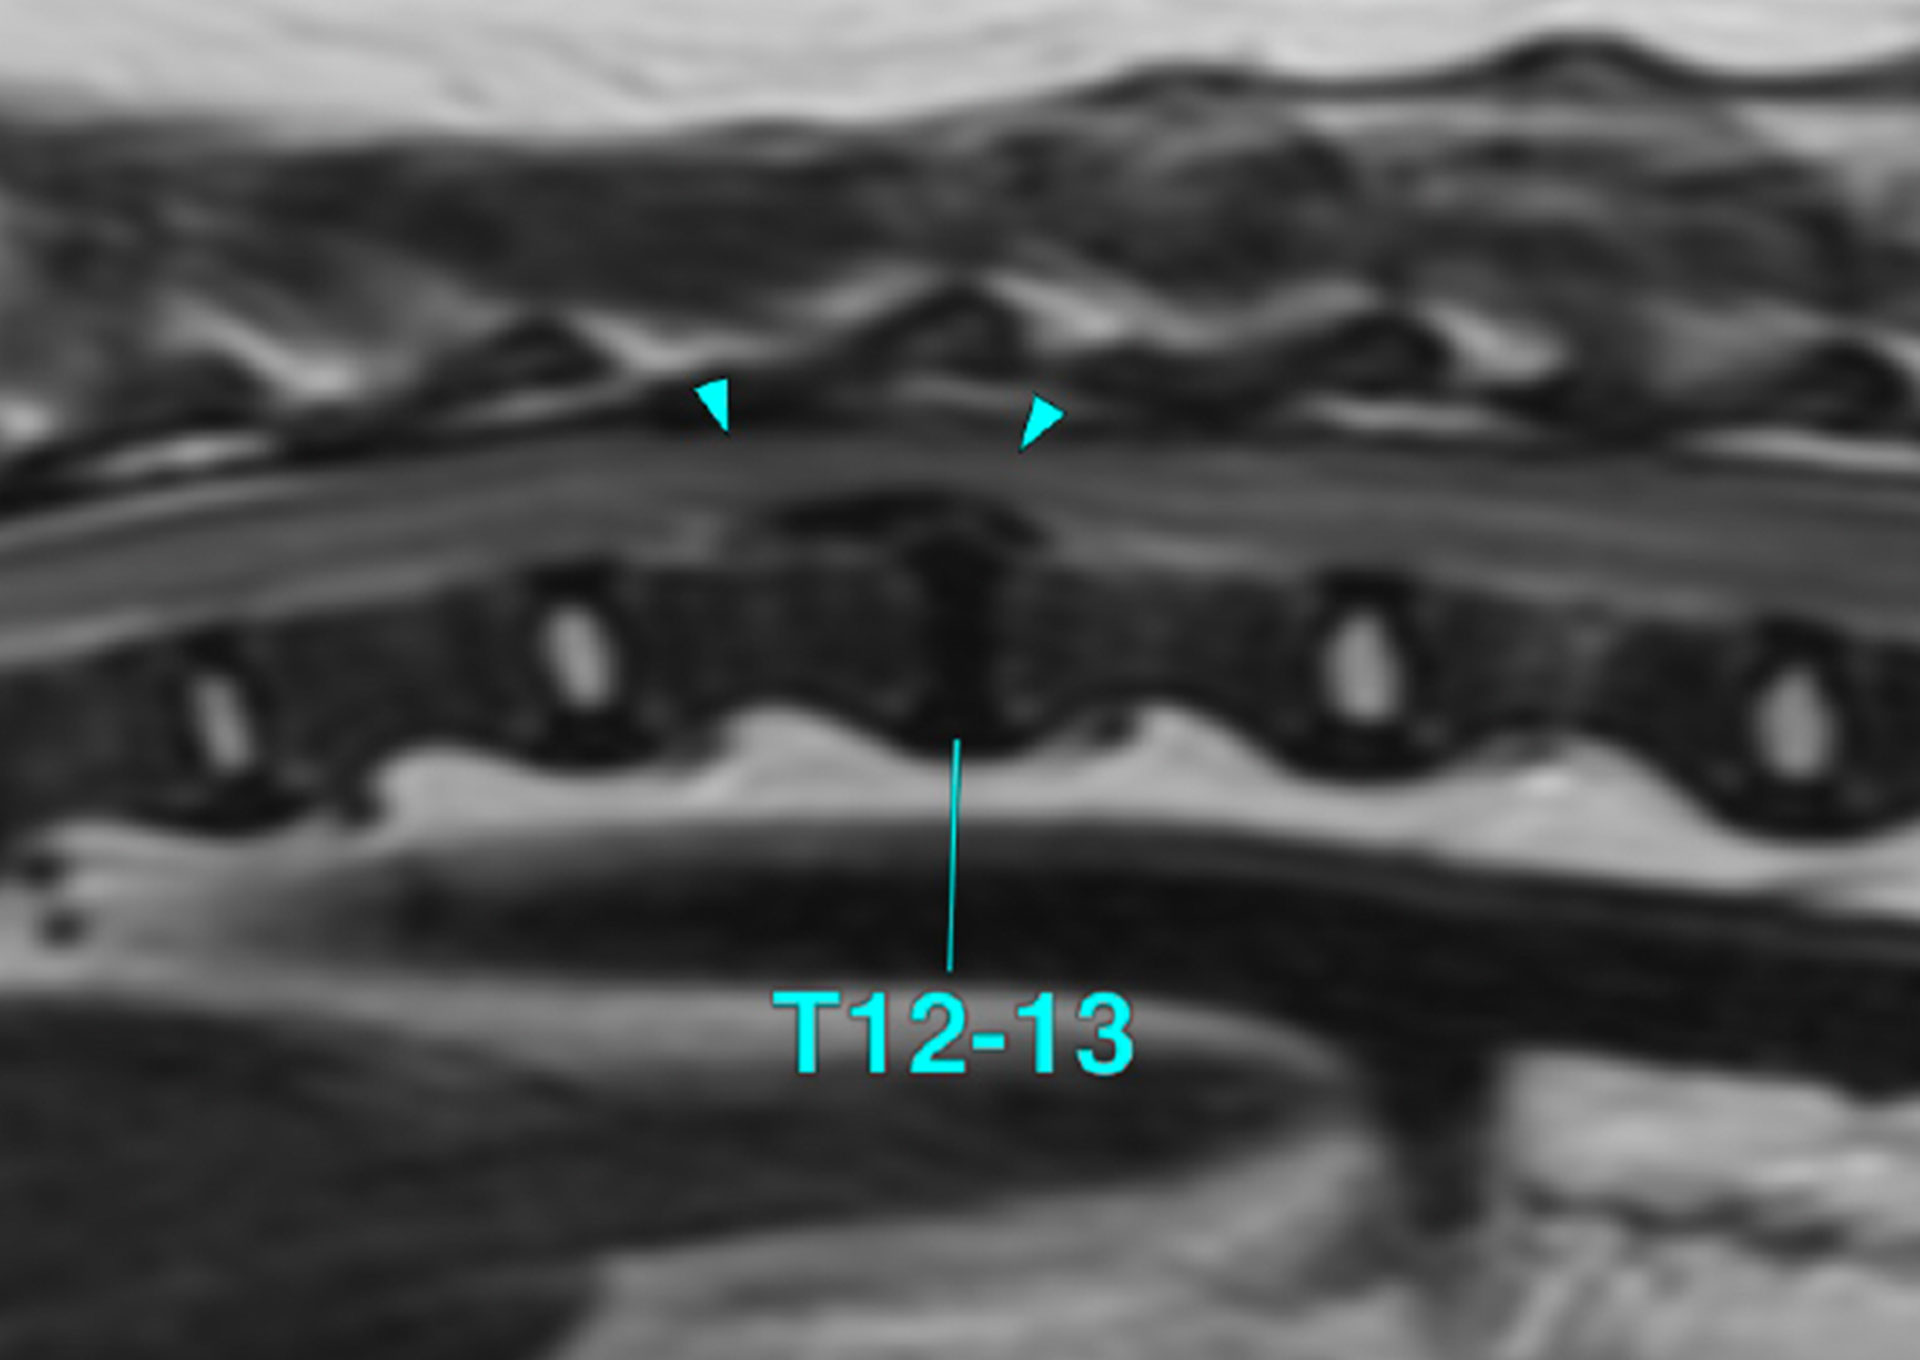

椎間板ヘルニア(グレードV)

に対する外科治療

椎間板ヘルニアの中でも、グレードVは重度の神経障害を伴い、迅速かつ適切な外科治療が求められる状態です。

当院では、椎間板ヘルニアの中でもグレードVの重症例に対する外科治療にも対応してきました。

これまでに200症例以上の椎間板ヘルニア手術を行ってきた経験をもとに、症例ごとの状態を慎重に評価し、適切な術式を選択しています。

ヘミラミネクトミーやベントラルスロット法など、症例に応じた手術方法を選択し、神経への負担を最小限に抑えることを重視しています。

術後の回復や生活の質を見据え、術前から術後管理まで一貫した体制で対応しています。